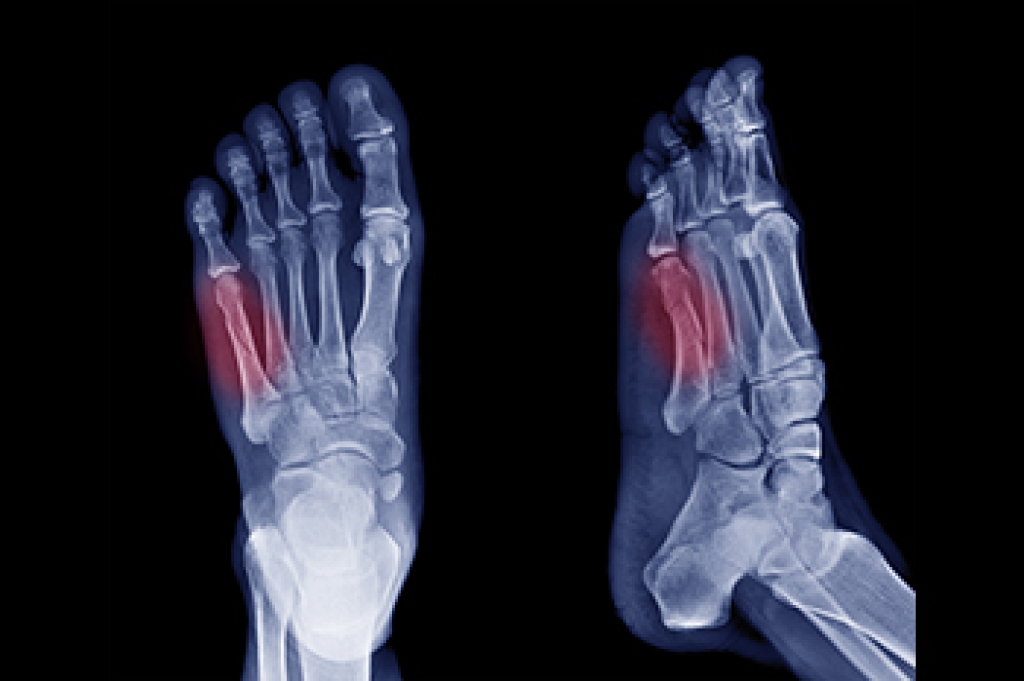

Arthritic Foot Care

Arthritis is a term that is commonly used to describe joint pain. The condition itself can occur to anyone of any age, race, or gender, and there are over 100 types of it. Nevertheless, arthritis is more commonly found in women compared to men, and it is also more prevalent in those who are overweight. The causes of arthritis vary depending on which type of arthritis you have. Osteoarthritis for example, is often caused by injury, while rheumatoid arthritis is caused by a misdirected immune system.

Arthritic symptoms range in severity, and they may come and go. Some symptoms stay the same for several years but could potentially get worse with time. Severe cases of arthritis can prevent its sufferers from performing daily activities and make walking difficult.